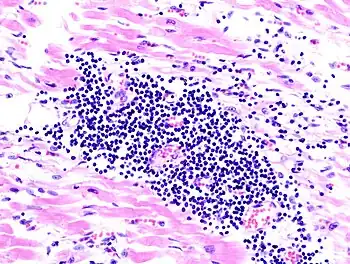

Endomyocardial biopsy specimen with extensive eosinophilic infiltrate involving the endocardium and myocardium (hematoxylin and eosin stain)